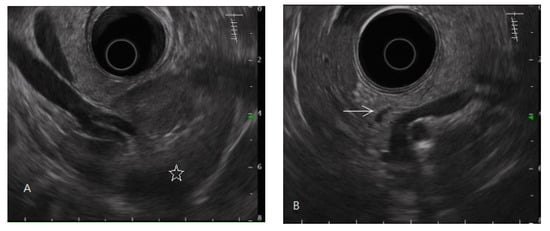

In this study, the diagnosis of pancreatic fibrosis was pancreatic ARFI value > 1.4 m/s (mean of 10 measurements in pancreatic head or body) [16] or meeting the EUS diagnostic criteria of early chronic pancreatitis. EUS-diagnosed early chronic pancreatitis has at least three of the seven total factors of the EUS criteria for early chronic pancreatitis proposed by the Japan Pancreas Society (JPS). The seven factors are lobularity with honeycombing, lobularity without honeycombing, hyperechoic foci without shadowing, stranding, cysts, dilated side branches, and hyperechoic main pancreatic duct margin [35], illustrated by normal and abnormal images in Figure 1 and Figure 2, respectively.

Figure 1.

Endoscopic ultrasonography of a normal pancreas. The normal pancreatic parenchyma is homogeneous, and the main pancreatic duct edge is non-hyperechoic. (A) Pancreatic tail, body; spleen (star mark), splenic vessels. (B) Pancreatic body, neck, partial main pancreatic duct (arrow mark). (C) Pancreatic head, uncinate process (hypoechoic ventral part, arrow mark); gallbladder; partial main pancreatic duct. (D) Pancreatic head; gallbladder (star mark); main pancreatic duct (arrow mark).